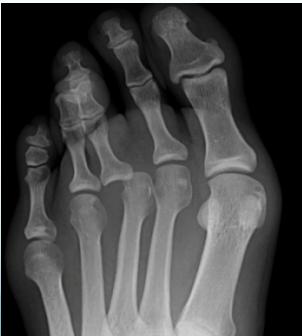

Fingers / Toes Dislocations

Common Causes:

• Sports, ball games, falls

Treatment:

• Reduction: Traction & counter traction

• Immobilization: Finger splint or buddy taping (with next finger/toe)